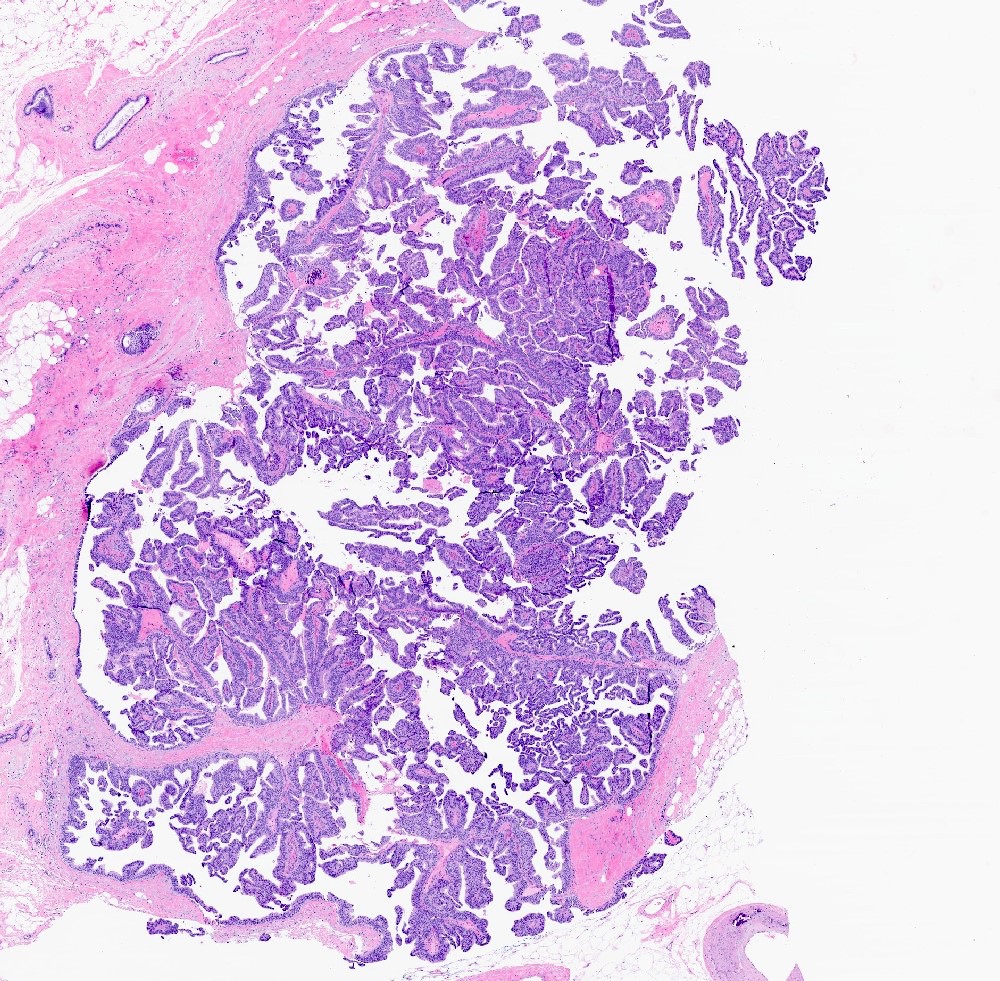

- Papillary tumor with pushing borders, may be within a cystically dilated duct, surrounded by a thick fibrous capsule (Histopathology 2008;52:20, Mod Pathol 2021;34:1044, Virchows Arch 2022;480:5)

- Delicate papillary fronds with fibrovascular cores lined by cuboidal to columnar epithelial cells with low to intermediate grade atypia

- Cribriform and solid architecture may be present

- Low mitotic activity (average 3 mitoses per 10 high power fields [HPFs]) (Am J Surg Pathol 2011;35:1)

- Most show complete lack of myoepithelial cells along the papillae and around the periphery of the tumor (Am J Surg Pathol 2006;30:1002, Am J Surg Pathol 2011;35:1)

- Basement membrane markers (collagen IV, laminin) may be expressed around the periphery (Pathobiology 2021;88:359, Am J Clin Pathol 2009;131:228)

- Invasive carcinoma is defined as the presence of neoplastic cells infiltrating beyond fibrous capsule (Mod Pathol 2021;34:1044)

- Most commonly invasive carcinoma of no special type (IDC NST), small (pT1), ER+, HER2- and low grade (Am J Surg Pathol 2011;35:1093, Breast J 2021;27:209, Breast J 2019;25:539, Curr Probl Cancer 2018;42:291)

- Staging is based on the size of the conventional invasive component if present

- Epithelial displacement / entrapment of neoplastic cells within capsule can occur and must be distinguished from true invasion beyond the fibrous capsule

Microscopic (histologic) images

Contributed by Kristen E. Muller, D.O. , Mariel Molina Nunez, M.D. and Julie Jorns, M.D. (Case #518)